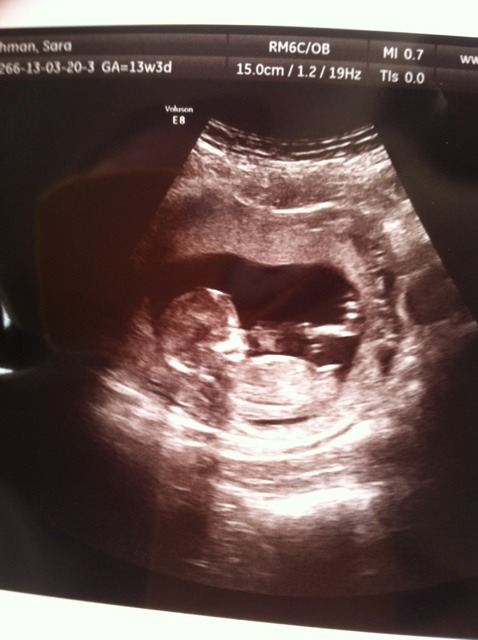

Pretty positive now! My bf leaves for basic soon and wanted to see the baby as he hasn't been able to go to the other scans. Attachment 9785Attachment 9786